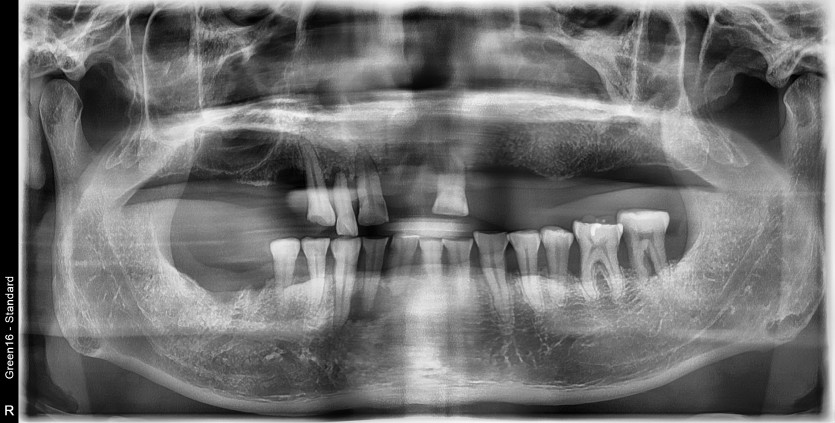

만 48세 상악 전체 임플란트 증례

상악 전체 임플란트 증례입니다. (하악 일부)

12개의 임플란트로 완성하였습니다.